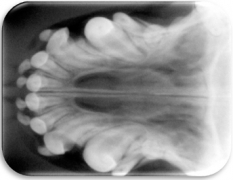

- Radiográfico (analógico y digital)

El diagnóstico clínico oral es de suma importancia ya que el plan de tratamiento y el pronóstico dependen de un certero y profundo análisis de los signos de la cavidad oral. Nuestra principal preocupación es atender los problemas que se encuentran en cavidad oral pero además siempre realizamos un detallado análisis de la función general del paciente. En nuestro centro revisamos de manera general a la mascota detectando cualquier problema sistémico. Contamos con un laboratorio de análisis clínicos en donde se realizan biometría hemática, química sanguínea, examen general de orina y pruebas para detección de enfermedades virales y de otros microorganismos. Contamos también con un laboratorio de histopatología en donde se revisa el material biológico para la detección y el diagnóstico de cambios morfológicos y lesiones en los tejidos. En lo que respecta al diagnóstico de la boca, contamos con un expediente donde se vacía toda la información dental y bucal de tal manera que mantenemos el control del tratamiento odontológico desde el inicio hasta el final y en donde el propietario o el médico que nos recomienda puede revisar en detalle toda la información recabada. Contamos con todo el instrumental y el equipo necesario para el diagnóstico de el aparato estomatognático (cavidad oral con dientes, tejidos de sostén y tejidos blandos, además de las estructuras relacionadas como articulación temporomandibular, cavidad nasal, cavidad orbitaria, etc.). Contamos con luz similar a la ultravioleta para diagnóstico de lesiones dentales por transluminación, pulpómetro para diagnóstico de vitalidad pulpar, localizador de ápices para tratamiento de conductos y equipo radiográfico tanto analógico como digital.

PERIODONTOGRAMA Y ODONTOGRAMA